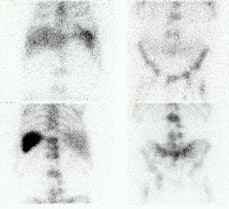

L5 vertebral osteomyelitis: The case below also illustrates the decreased sensitivity of In-111 WBC imaging for the detection of vertebral osteomyelitis. Bone scan revealed increased tracer activity within L5 (red arrow) in a patient with osteomyelitis at this level. The In-111 WBC exam demonstrated no evidence of increased tracer accumulation in L5 (blue arrow). Case submitted by Dr. Marc Cote, D.O. |

|